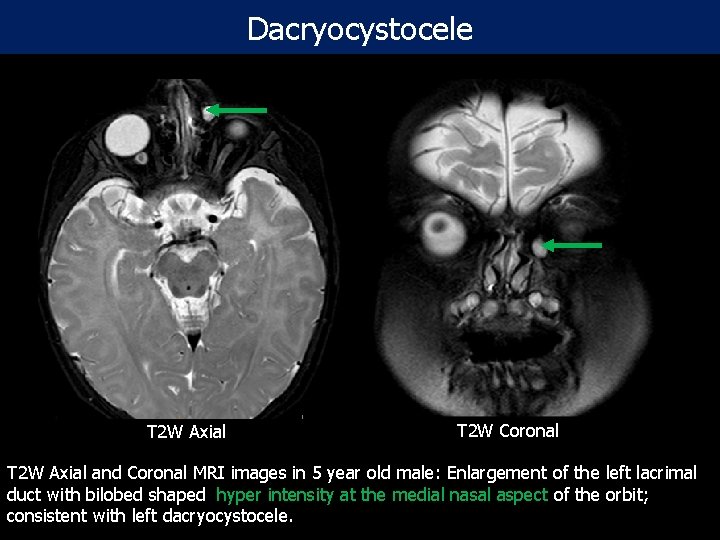

Dacryocystocele T 2 W Axial T 2 W Coronal T 2 W Axial and Coronal MRI images in 5 year old male: Enlargement of the left lacrimal duct with bilobed shaped hyper intensity at the medial nasal aspect of the orbit; consistent with left dacryocystocele.